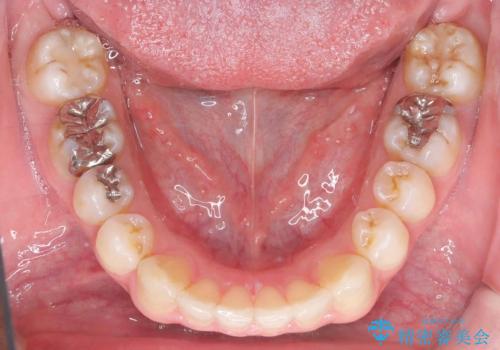

- 前歯の隙間と歯のデコボコを主訴にご来院された患者様です。

加えて、上下の奥歯が全く咬み合わないシザーズバイトの状態も認められました。

矯正検査の結果、非抜歯でインビザラインによる治療が可能と判断し、治療を行いました。

歯の隙間とデコボコ、シザーズバイトも改善され、咬み合わせや見た目が整い、患者様にも大変ご満足いただけました。